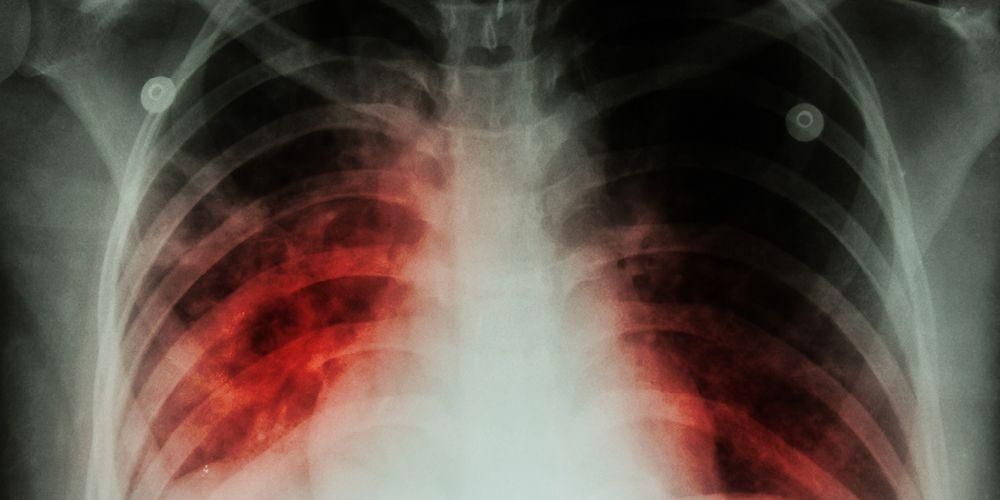

Infeksi paru-paru bisa saja terjadi pada Anda ataupun orang-orang terdekat Anda. Berbagai macam infeksi paru-paru mengintai di setiap waktu dengan penyebab infeksi paru-paru yang berbeda-beda. Infeksi paru-paru terbagi menjadi dua berdasarkan daerah yang diinfeksi, yaitu infeksi paru-paru di pernapasan bagian atas dan infeksi paru-paru di pernapasan bagian bawah. Infeksi paru-paru di pernapasan bagian atas terjadi pada bagian laring ke atas. Sedangkan infeksi paru-paru di pernapasan bagian bawah meliputi bagian laring ke bawah. Penyebab infeksi paru-paru dan gejala utama yang dialami oleh penderita juga berbeda tergantung dari lokasi terjadinya infeksi.Infeksi paru-paru di pernapasan bagian bawah yang umum terjadi adalah pneumonia, bronkiolitis, tuberkulosis, dan bronkitis. Infeksi paru-paru di pernapasan bagian atas biasanya meliputi tonsilitis, pilek, laringitis, dan infeksi sinus.Flu juga termasuk salah satu infeksi paru-paru yang cukup terkenal dan uniknya, flu bisa menginfeksi paru-paru di pernapasan bagian atas dan bawah.

Di luar dari lokasi dan jenis infeksi paru-paru yang menyerang, penyebab infeksi paru-paru umumnya adalah bakteri atau virus. Jenis infeksi paru-paru yang cukup sering dijumpai adalah pneumonia, bronkiolitis, dan bronkitis.Meskipun jarang, penyebab infeksi paru-paru dapat ditimbulkan oleh infeksi jamur, seperti Histoplasma capsulatumPneumocystis jirovecii, dan Aspergillus. Salah satu mikroorganisme penyebab infeksi paru paru lainnya adalah mycoplasma yang memiliki ciri dari bakteri dan virus.Meskipun seringnya penyebab infeksi paru-paru adalah virus atau bakteri, tetapi infeksi paru paru makin meningkat risikonya saat seseorang mengalami peradangan atau alergi pada pernapasan atau paru-parunya.Peradangan dan alergi dapat diakibatkan oleh zat-zat atau benda di lingkungan sekitar, berupa zat kimia, uap atau asap, benda pemicu alergi, debu, polusi udara, dan asap rokok.